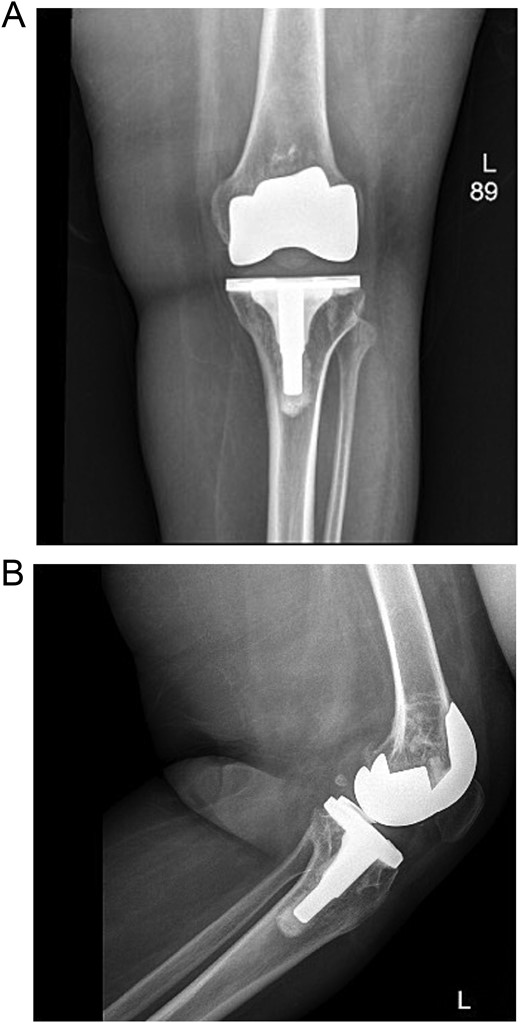

Post-operatively, the patient was seen by a physiotherapist and started immediate weight-bearing and range-of-motion exercises. She was seen in the clinic after 6 weeks, and reported significant relief of symptoms and satisfaction with the outcome (Fig. 6).

(A) Anteroposterior view of the left knee post revision and polyethylene replacement. (B) Lateral view of the left knee post revision and polyethylene replacement.